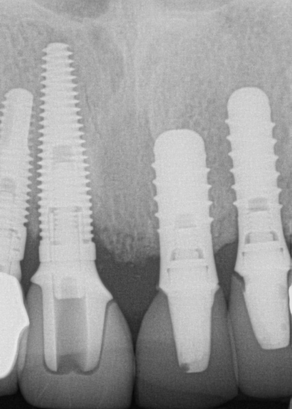

The next case follows the digital protocol for fully guided surgery and prosthetics. A CBCT radiograph, digital impression, and digital photography were the cornerstones to the success of this case. The 3D data set was electronically delivered to the dental laboratory. The data were merged and the process to develop the plan was initiated. The use of CBCT was essential in this case, particularly due to minimal space for placement of individual implants and single-unit crowns. The patient's chief concern was that she wanted to have single-unit crowns instead of fixed crown-and-bridge restorations because she was worried that she would someday find herself in an assisted-living facility; if that were to happen, she wondered, who would help floss under her bridge work? Her decision was to have single implants with individual crowns. CBCT technology is much more accurate in evaluating space maintenance and management.10 Periapicals in the past were rather close for calculating spacing; however, the CBCT identifies the buccal-lingual dimensions as well as the mesial-distal measurements. On review of the completed proposals for implant placement and provisionals, it was determined that there was sufficient spacing for implant placement to allow appropriate emergence profiles for the provisionals and then eventually the final single-unit cemented crowns. The proposal was accepted, and a 3D-printed surgical stent was fabricated, along with the PMMA provisionals (Figure 29 through Figure 35).

Fig 29. Preoperative Panorex.

Figure 29

Fig 30. Preoperative periapical radiograph.

Figure 30